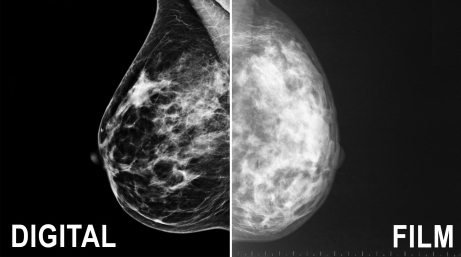

Advanced 3D Mammography for Every Woman

Our 3D mammograms, contrast-enhanced mammograms, and no-compression Vera Scan Breast CT provide more detailed imaging than traditional 2D mammograms, helping detect even the smallest abnormalities. Our advanced technologies offer more accuracy and comfort for patients with dense breast tissue, prior surgery, or implants.